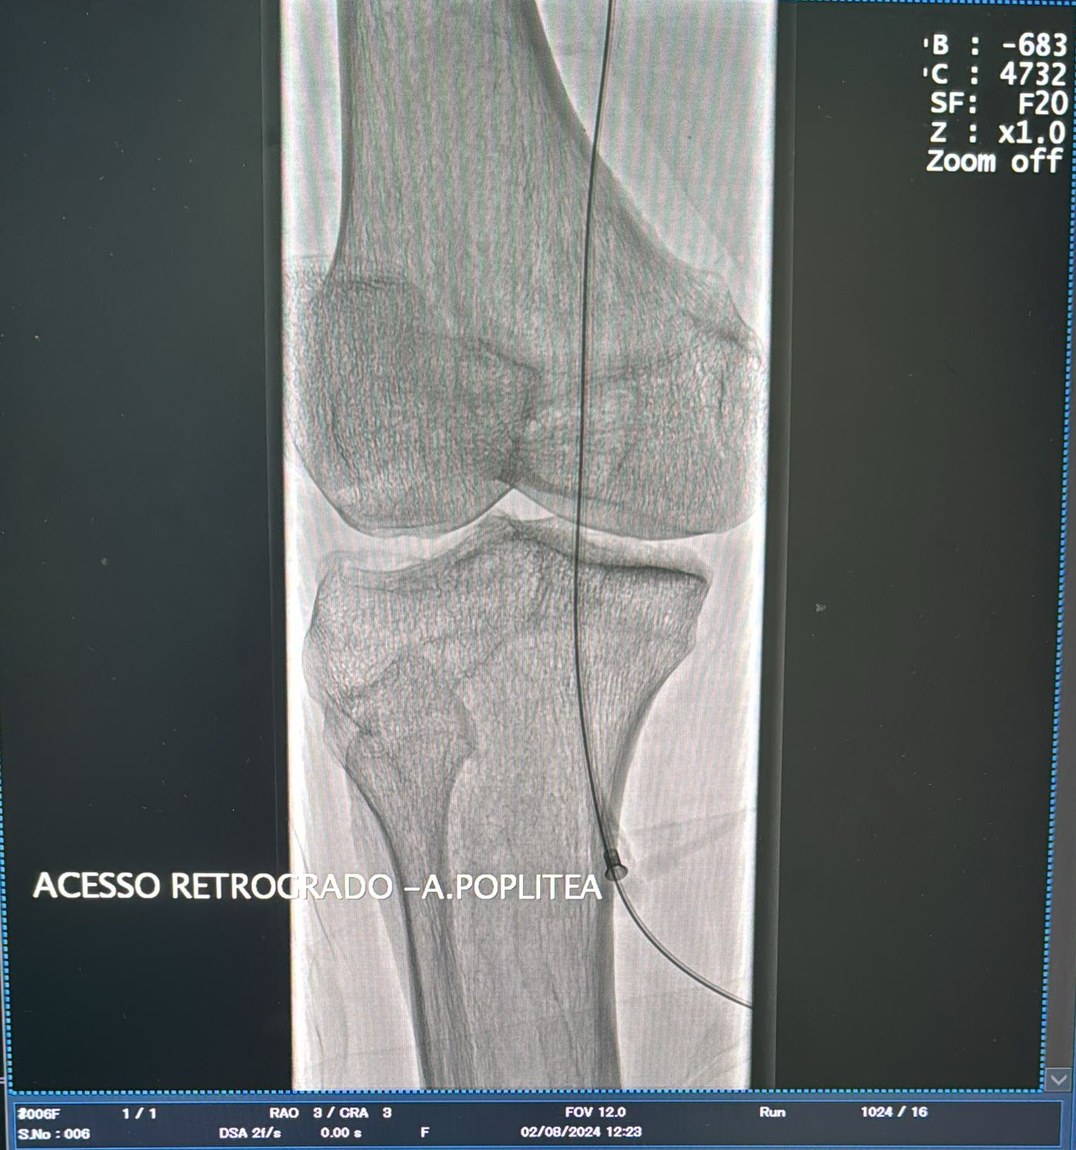

O serviço de Hemodinâmica, instalado no Complexo Hospitalar Deputado Janduhy Carneiro, em Patos, e gerenciado pela Fundação Paraibana de Gestão em Saúde (PB Saúde) realizou um procedimento inédito na unidade, que contribuiu para salvar mais um paciente no Sertão da Paraíba. Trata-se de uma angioplastia femoro-poplítea com punção retrógrada, um tratamento alternativo para desobstruir as artérias responsáveis pela circulação de sangue nas pernas, evitando a amputação dos membros.

Conforme destacou o especialista, a equipe médica tentou, primeiramente, outras técnicas mais comuns para executar o procedimento. “O normal é acesso contralateral ou homolateral anterógrado para a realização desse tipo de procedimento. Depois de tentarmos contralateral e punção anterógrada, definimos, então, acessar a artéria poplítea guiados por ultrassom e ultrapassamos a lesão de forma retrógrada. Procedemos a angioplastia femoro-poplítea de forma retrógrada, tendo evoluído bem, com sucesso, com ressurgimento de pulsos distais e, consequentemente, salvamento do membro”, explicou.